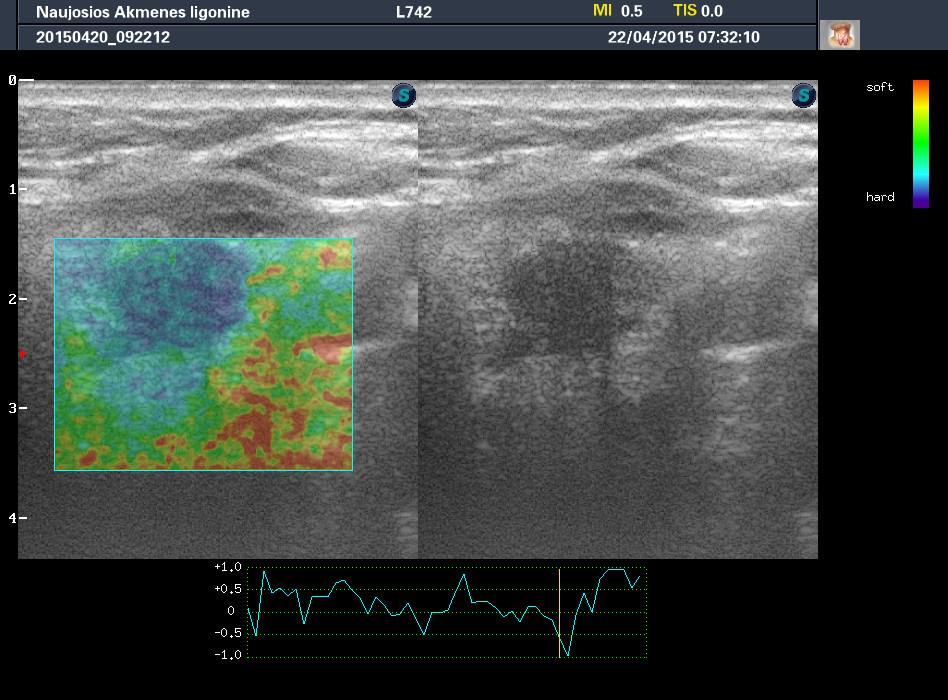

Случай 1

Женщина 67 лет, жалоб нет. Рост узла за год +3 мм. Регионарные ЛУ не увеличены.

apr222015073209_7.jpg

1-й узел злокачественный, а 2-й ,скорее всего, доброкачественный. Но,понятное дело, нужна пункция и было бы здорово узнать результат.

Mattiola писал(а): И,простите, что за исследование на сканах, не на видео? Я такого не делаю и,к сожалению, не знаю,как интерпретировать его(

Эластография. http://www.medison.ru/si/art380.htm